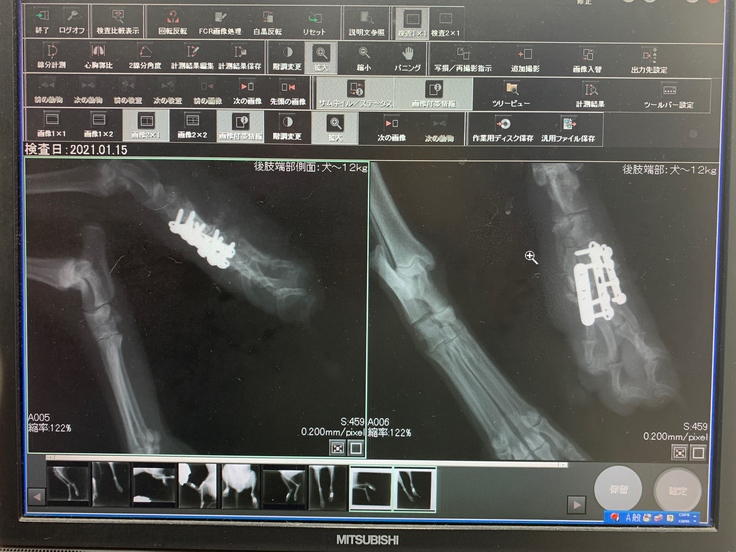

モモの左後ろ脚、人間の手首から手の甲にあたる部分の骨が粉々に砕けていたため、長時間に及ぶ複雑な手術になりました。

今でも金属のプレートが入っています。

術後、そしてリハビリ後、今では歩いたり走ったり...ごく普通の生活を過ごしています。